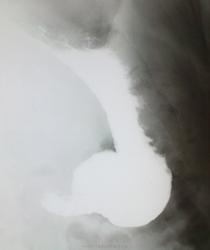

+1.Скорее всего, это не грыжа (пищеводного отверстия диафрагмы), а так получается пищеводая ампула( кратковременная картина "кольца сатурна "-инвагинация пищевода в пищевода - вариант нормы); т.к. дистальнее этого расширения видны тонкие пищеводные складки ( при грыже, были бы видны широкие желудочные складки слизистой).

ГПОД или нет - на откуп смотрящему. Рельеф слизистой гастритический: складки по большой кривизне разновеликие, неравномерные, избыточные, в антруме имеют косой ход (хотя полноценного раздувания двойного нет, судить адекватно не получится).